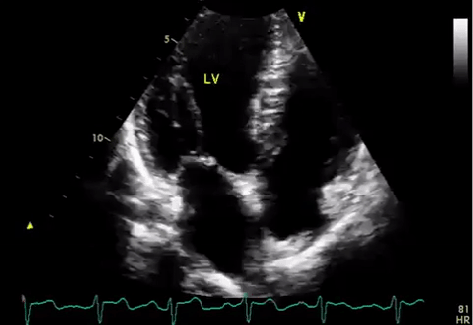

Normal Echo: Notice how the agitated saline bubbles remain on the right side of circulation and do not cross over. The bubbles were filtered out by the pulmonary vasculature.